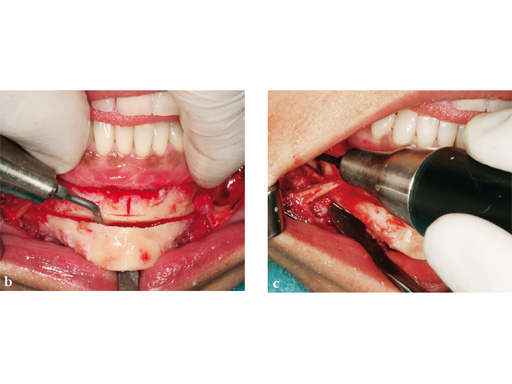

Case 2: Complex congenital deformity with distortion of alveolar processes and dentition, resulting in a 3.5 cm nonocclusion in the right maxillomandibular complex. Occlusion is exclusively controlled through the left second premolar to second molar. Piezosurgery was useful in this case due to complex anatomical deformities resulting in atypical positioning of the inferior alveolar canal on the right side. The cramped confines of dental and bony tissues in the deformed anatomy required an adequate type of osteotomy to do a significant yet controlled skeletal movement to overcome the vertical discrepancy intraorally, without changing the outer projection of the mandibular frame.

Case provided by Nils-Claudius Gellrich, Hannover, Germany